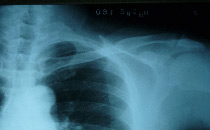

肩关节

例子

病症描述:强直性脊柱炎也会致使肩关节强直。不及时医治就会促进肩关节活动受限,它会影响患者梳头、抬手,大幅度动作不能动而影响平常活动等。肩关节强直主要是来源于肿胀,才会致使肩关节受限。